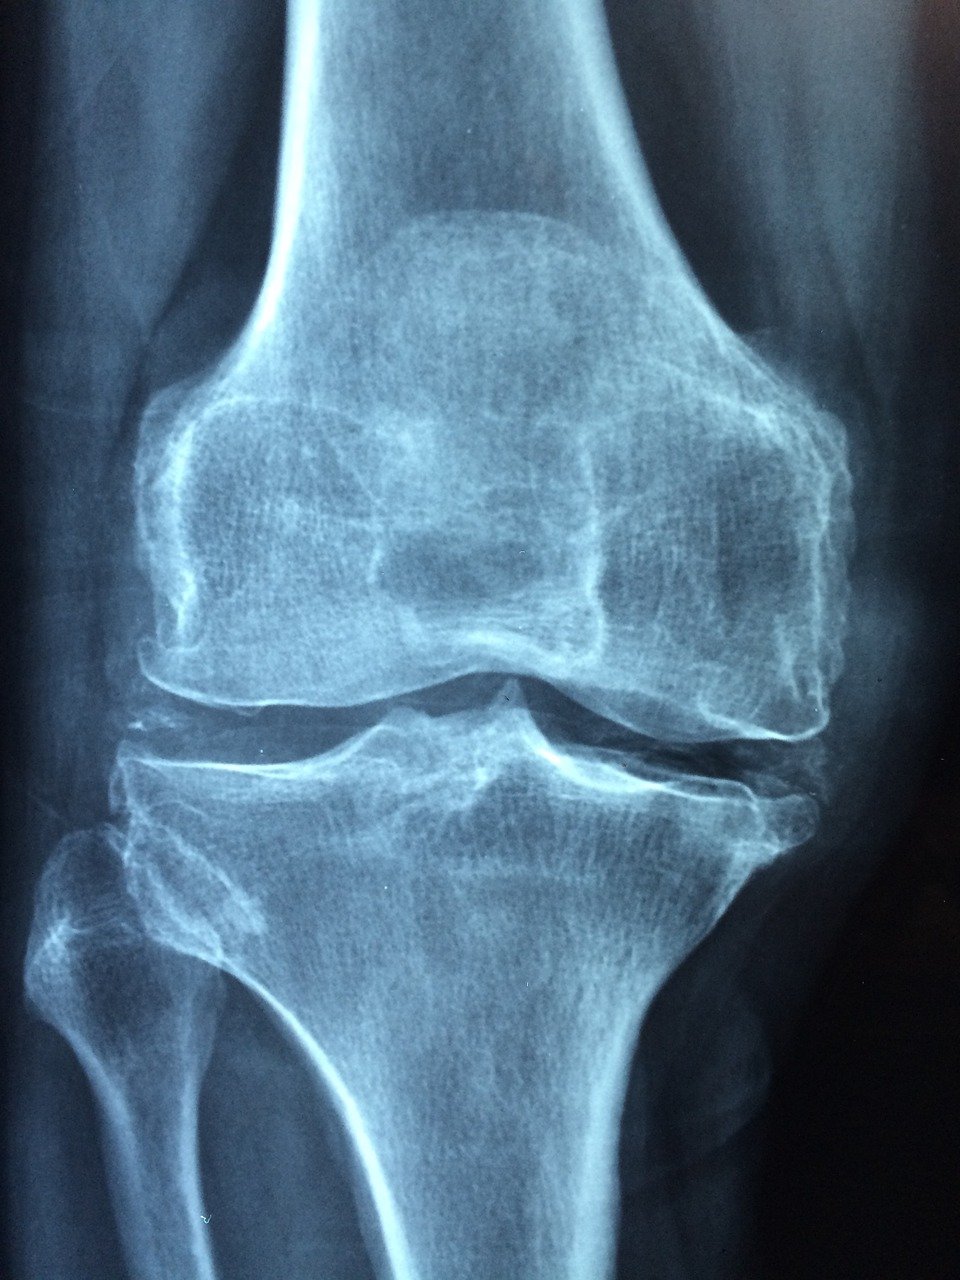

첫 번째는 '해리' 현상으로, 인공관절 플라스틱이 마모되면서 헐거워지는 증상이다. 보통 수술 후 10~15년이 지나면 나타나는 증상으로 주기적인 검진과 X-RAY 촬영으로 초기에 발견하면 재수술이 가능하다.